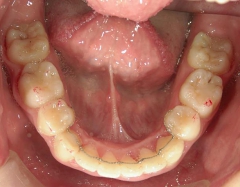

矯正_灰色.pngno.18_2196_治療前_下.jpg矯正_灰色.png

矯正_灰色.pngno.18_2196_治療後_下.jpg矯正_灰色.png